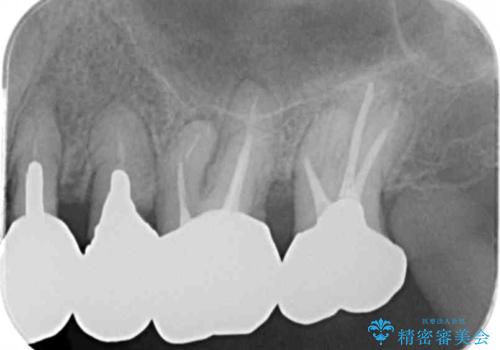

銀歯を除去したところ大臼歯は十分な歯質が残っていたため残すことができましたが、小臼歯の2本は虫歯の再発により残っている歯質が非常に少なく破折リスクが非常に高いと判断しました。

長期的な予後を見込むことが難しいため、相談の上抜去を行いインプラント治療を進めていくこととなりました。